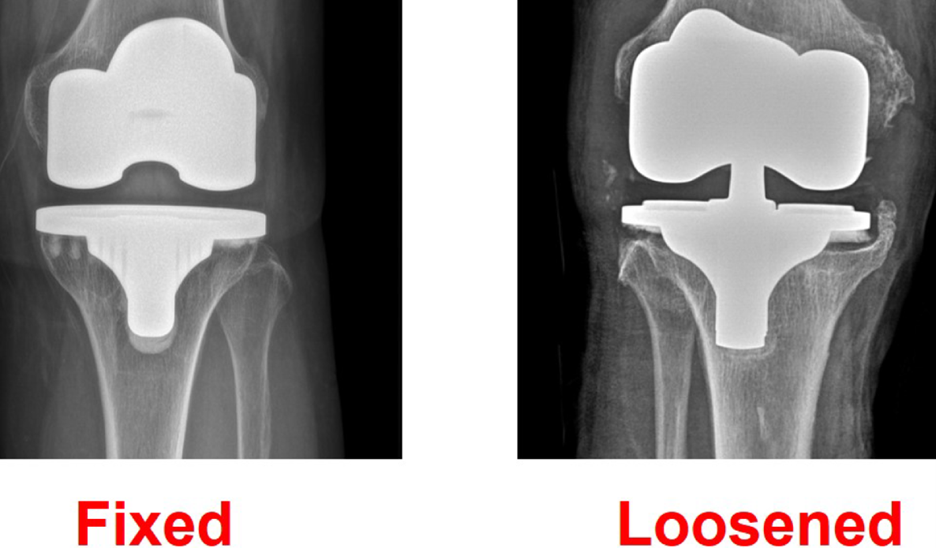

Implant Loosening

One of the possible causes of persistent pain is loosening of the artificial joint components. The prosthetic implant must remain firmly attached to the bone for stable movement. Over time, excessive stress, bone quality issues, or misalignment may cause the implant to loosen.

Patients with implant loosening often experience pain while walking, swelling around the knee, and difficulty putting weight on the affected leg.